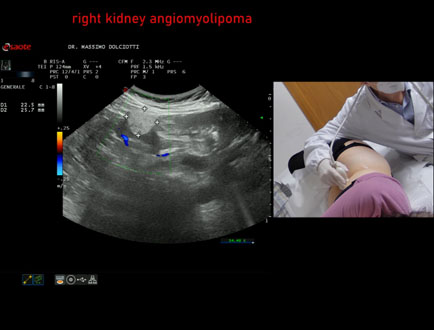

Data inserimento: 03/04/2026

Ecografia del: 12/03/2026

Strumento: Esaote MyLab Eight

Sonda: Convex Multifrequenza 1-8 MHz

Età Paziente: F 66 anni

Motivazione dell'esame: follow up per angiomiolipoma renale destro

Commento all'esame: le immagini ed il video documentano al rene destro, in sede corticale polo inferiore, immagine iperecogena, a margini definiti, delle dimensioni di 25 x 23 mm, senza segni di vascolarizzazione, da ricondurre, come prima ipotesi, ad angiomiolipoma.

Conclusioni: angiomiolipoma del rene destro (angiomyolipoma of the right kidney).

In collaborazione: Dr.ssa Marica Manfredi - Ancona, Dr. Ilir Qose - Ancona

Presentazione: Dr. Massimo Dolciotti - Ancona

Elaborazione digitale: Andrea Dini - Ancona